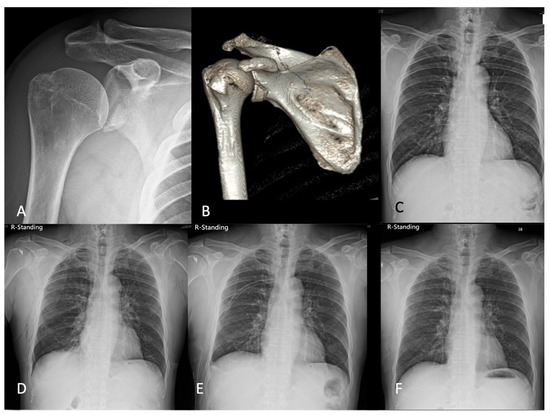

2.1. Case 1